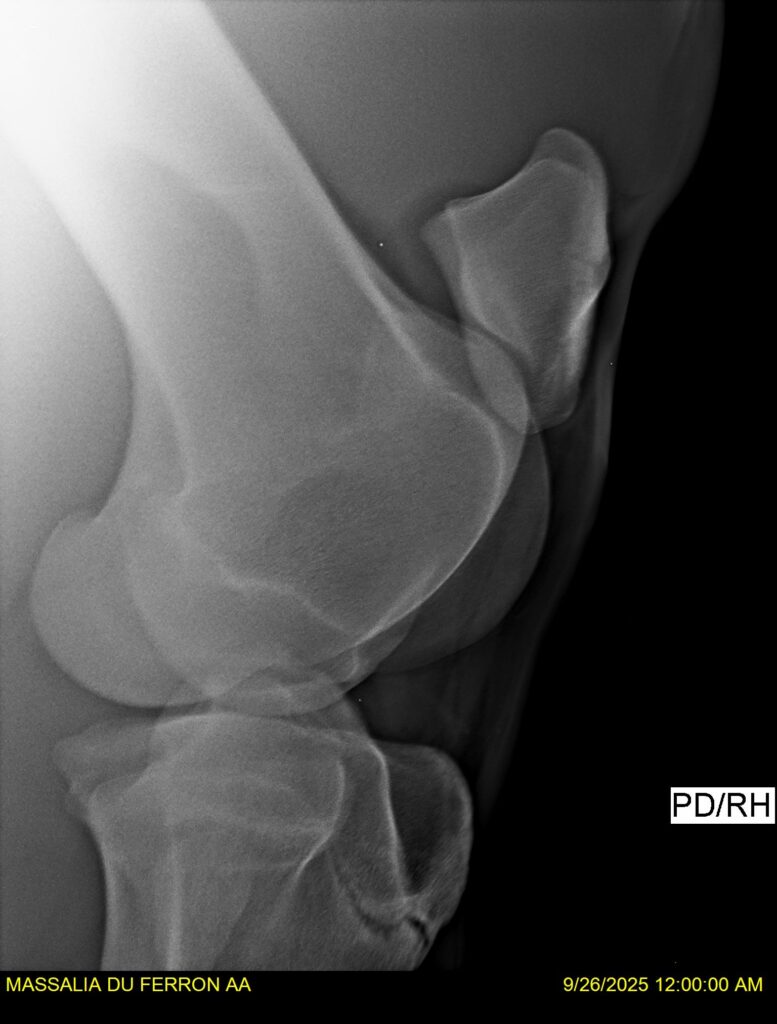

MASSALIA DU FERRON, jument qui prendra 4 ans par PRESTIGE KALONE x TRESOR DU RENOM. Un mental en or et un véritable sens de la barre ! Facile d’accès ! Bonne énergie et bons moyens. Souche moderne et très intéressante. Transport OK, maréchalerie OK, santé RAS, Bilan clichés radios OK.

RADIOS et COMPTE RENDU